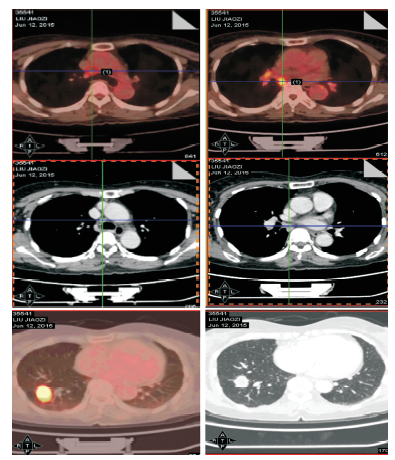

聂强:患者服用克唑替尼28天后复查PET/CT, 总体疗效部分缓解(缩小58.3%), 原发病灶在大小、SUVmax、淋巴结SUVmax都有所下降, 重新分期为右下肺癌 yT1aN0M0Ⅰ A期。

聂强:评价后拟行右下肺叶切除术+肺门纵隔淋巴结清扫术, 术中我们发现患者叶间淋巴结与中叶动脉粘连, 难以分离, 决定行中下肺叶切除术+肺门纵隔淋巴结清扫术。术后病理提示:右下肺浸润性腺癌, Ⅱ 级; 淋巴结转移共3/20。新辅助治疗前后FISH检测ALK基因断裂分别为78%和63%。